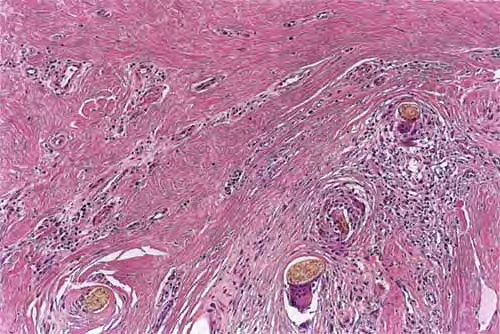

Read MoreAcne keloidalis nuchae =العد الجدري Acne keloidalis nuchae The histological findings vary depending on the timing of the biopsy. The initial infiltrate is primarily composed of neutrophils and lymphocytes that are distributed around the lower infundibulum and isthmus of the hair follicle. Subsequently, the follicle and sebaceous glands are destroyed, with liberation of the […]